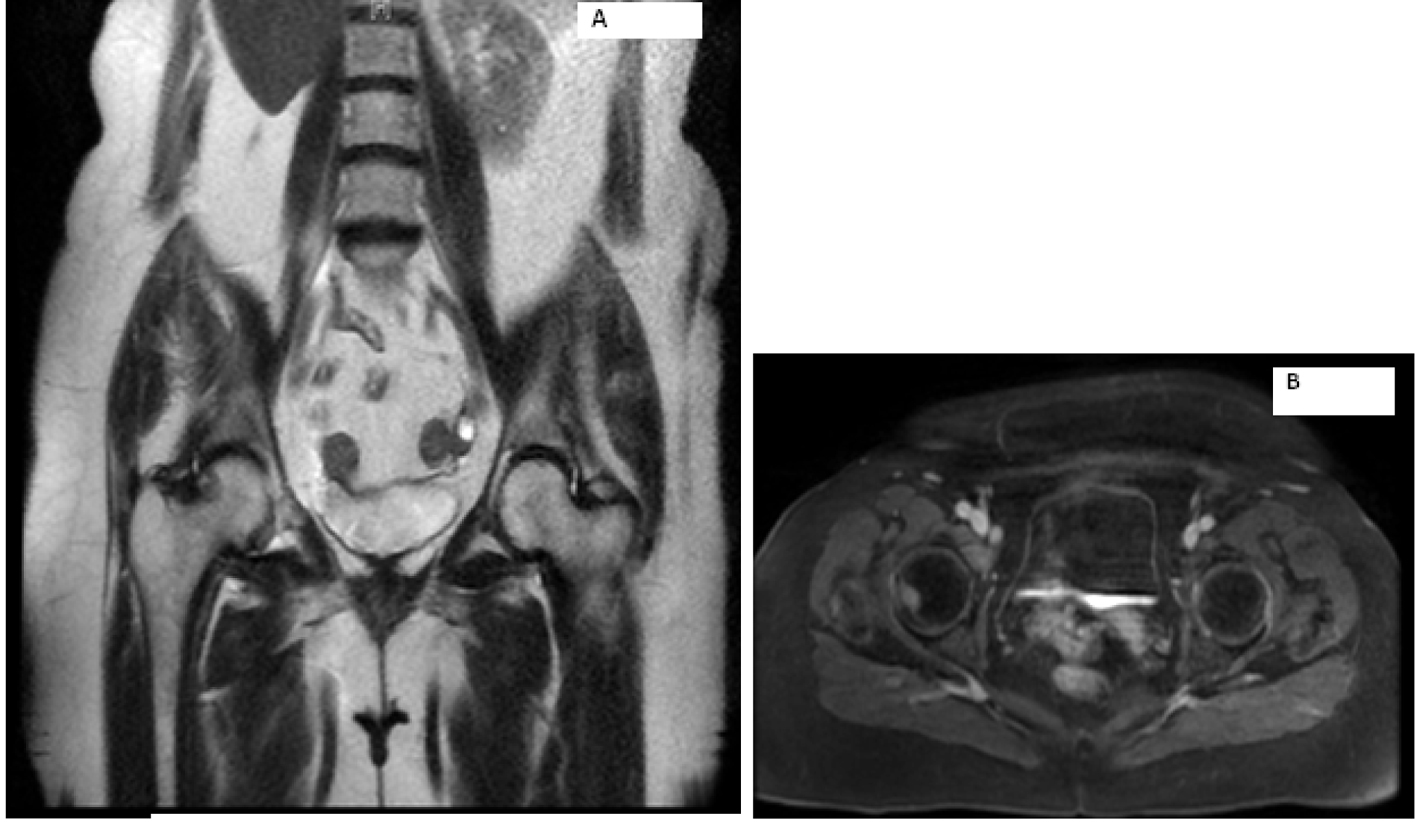

Laboratory work-up includes normal complete blood count and comprehensive metabolic panel. Serum calcium, parathyroid hormone level and TSH were within normal limits. Her 24-h urine catecholamines were elevated: metanephrines 683 mg/24 h (normal range: 30 - 180 mg/24 h), normetanephrines 6,391 mg/24 h (normal range: 148 - 560 mg/24 h), total metanephrines 7,074 mg/24 h (normal range: 180 - 646 mg/24 h), epinephrine 11 mg/24 h (normal range: < 21 mg/24 h), norepinephrine 151 mg/24 h (normal range: 15 - 80 mg/24 h) and dopamine 605 mg/24 h (normal range: 65 - 400 mg/24 h). Plasma normetanephrines (free) was 18 nmol/L (normal range: < 0.09 nmol/L) and chromogranin A, S was 527 ng/mL (normal range: < 93 ng/mL). Magnetic resonance imaging (MRI) of the abdomen and pelvis revealed metastatic disease in bilateral proximal femurs, vertebrae and iliac bones (Fig. 2, 3). Patient was also tested for RET mutation, and was found to be negative for the same.

![]() Click for large image | Figure 2. Magnetic resonance imaging of the abdomen showing metastasis to right hip. |

![]() Click for large image | Figure 3. Magnetic resonance imaging of the abdomen showing (A) empty right adrenal and renal fossa and (B, C) metastasis seen in the vertebrae. |